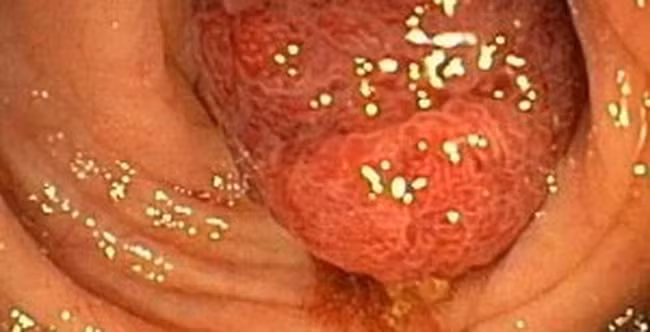

Ngủ đủ sẽ giảm nguy cơ ung thư ruột già. Ngủ dưới 6h mỗi đêm tăng 50 % nguy cơ bị bệnh polyp ruột già so với ngủ ít nhất 7h mỗi đêm. Polyp nếu không điều trị có thể chuyển thành ung thư.